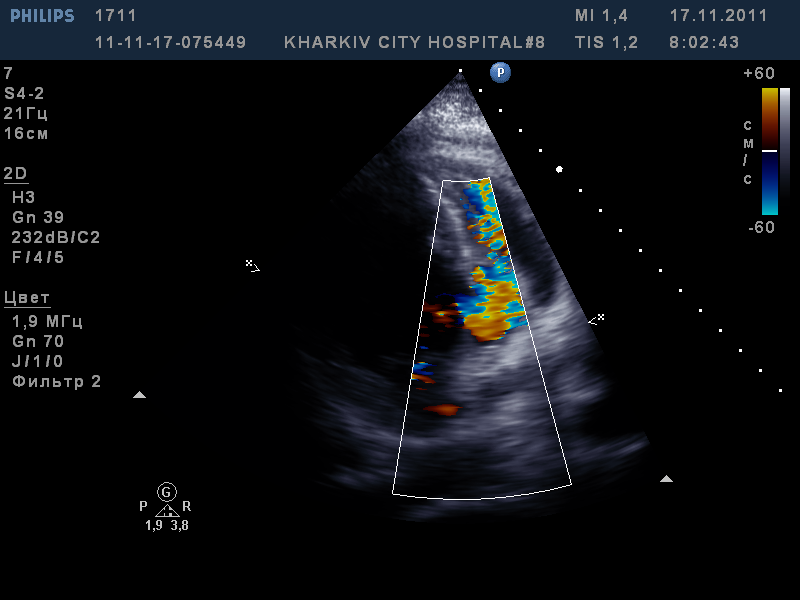

поступила пациентка в инфарктное отделение с передним инфарктом. Сегодня делал ЭХО-КС.

Выявлено расслоение межжелудочковой перегородки со сбросом в правый желудочек. Имеется отслойка листков перикарда- гидроперикард.

Снимки не отображают реальную картину, необходимо смотреть видео.